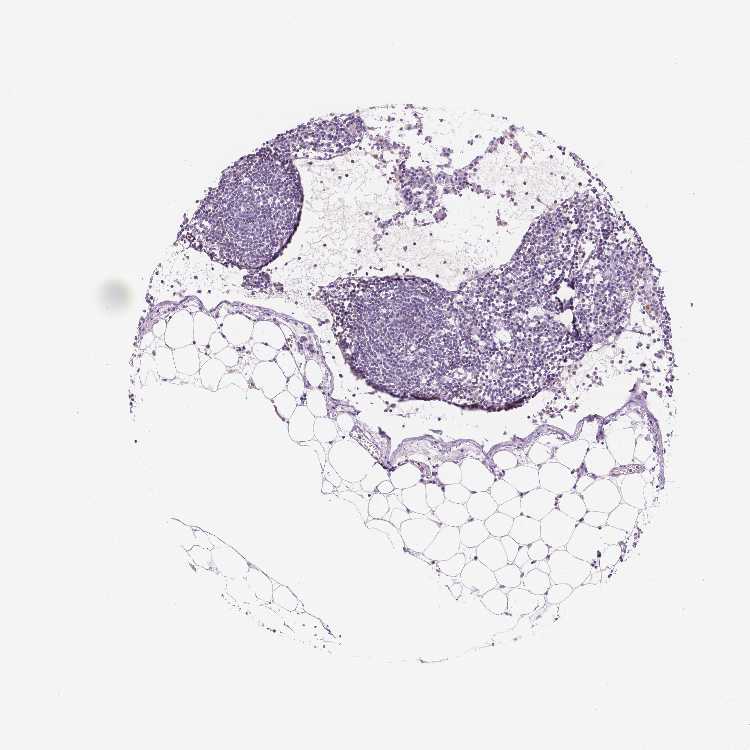

TISSUE PRIMARY DATA LYMPH NODE Show tissue menu

Lymph node

Tissue proteome

Lymphoid tissue

LYMPH NODE - Antibody stainingi

Antibody staining in the annotated cell types in the current human tissue is reported as not detected, low, medium, or high, based on conventional immunohistochemistry profiling in selected tissues. This score is based on the combination of the staining intensity and fraction of stained cells.

Each image is clickable and will lead to virtual microscopy that enables deeper exploration of all samples and also displays staining intensity scores, fraction scores and subcellular localization as well as patient and tissue information for each sample.

Information about each individual sample is listed below, including gender, age, a tissue section image and estimated fractions of cell types. nTPM (normalized transcripts per million) values give a quantification of the gene abundance which is comparable between different genes and samples.